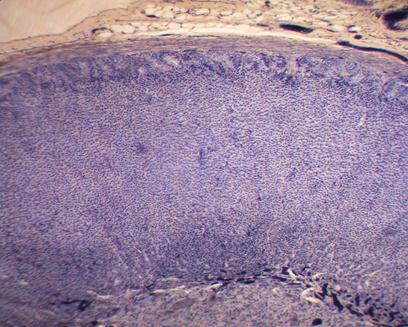

Фото. 3.4.2. Надпочечник. Гем.-Эоз.

Малое увеличение. (Ув.10х7)

Фото. 3.4.3. Клубочковая зона коры надпочечника. Гем.-Эоз.

Большое увеличение. (Ув.40х7)

| «клубочки» корковых эндокриноцитов | |

Фото.3.4.4. Пучковая зона коры надпочечника. Железный гем.

Большое увеличение. (Ув.20х7)